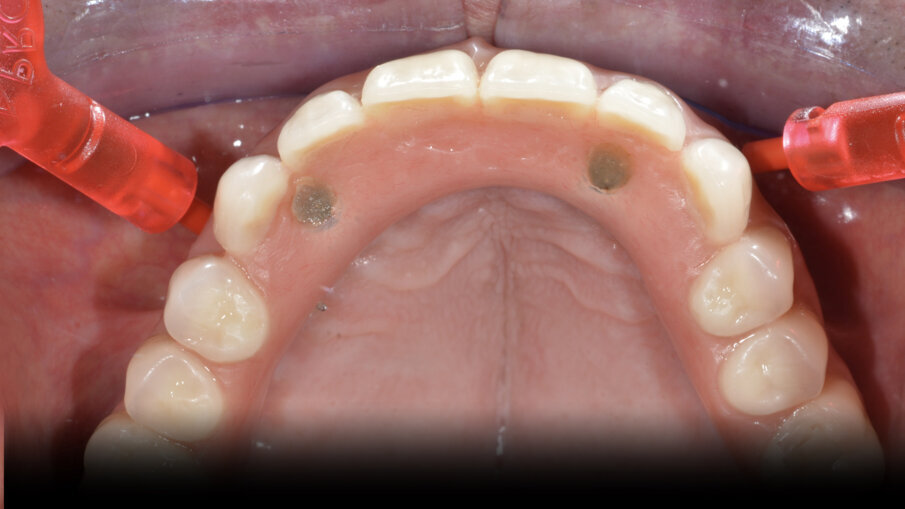

In particolare le polveri di glicina grazie al loro elevato potere antimicrobico e alla loro granulometria ridottissima, permettono un’accurata disinfezione a livello sopra e sub gengivale dell’intero cavo orale, soprattutto a livello del tragitto trasmucoso dell’abutment. In foto possiamo vedere un OT Equator (Rhein83, Italia) utilizzato per protesi fissa con la sistematica OT Bridge (Rhein83, Italia) (Figg. 5, 6). La rimozione totale del Biofilm batterico a livello sopra e sotto gengivale permette una “restitutio ad integrum” del tessuto gengivale, con una disinfezione profonda a livello tissutale.

Fig. 5_Manovre di air polishing su OT Bridge.

Fig. 6_Manovre di rimozione del biofilm batterico su OT Equator.

Mostriamo di seguito l’esecuzione di un lavoro di protesi ibrida su impianti tipo Toronto su sistematica OT Bridge (Rhein83, Italia). Il paziente, edentulo con più di 80 anni di età viene operato in chirurgia guidata (Figg. 11, 12). Vengono inseriti 4 impianti TSIII (Osstem, Korea) del diametro di 4 x 8.5 in zona 16, 3.5 x 11.5 in zona 12, 3.5 x 11.5 in zona 23 e 4 x 8.5 in zona 27. La progettazione è avvenuta con il software RealGuide (3Diemme, Italia) sfruttando le informazioni del montaggio dei denti della protesi totale. Nonostante la progettazione accurata, gli impianti non si sono potuti collocare in perfetto parallelismo per le condizioni ossee scarse. Quindi tra le varie fixture sono presenti disparallelismi, proprio per questo abbiamo deciso di utilizzare la sistematica OT Bridge (Rhein83, Italia) che risulta particolarmente vincente in caso di parallelismo tra i monconi. Abbiamo inserito gli abutment OT Equator (Rhein83, Italia) già al tempo della chirurgia e li abbiamo ricoperti con le viti di guarigione scegliendo la chirurgia one-stage (Figg. 13, 14).

Fig. 15_Ottimo stato di salute di OT Bridge allo smontaggio della vite di guarigione.